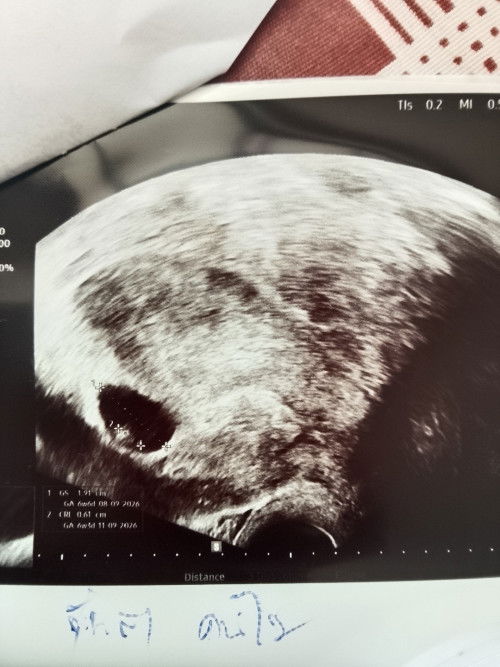

ตั้งครรภ์ 11 วีค มีเลือดออกสีน้ำตาลเมื่อวานมีอาการปวดท้องแต่วันนี้ไม่มีแล้ว อันตรายไหมคะ

เมื่อวานเราทางด้วยบีทีเอสและเดินค่อนข้างเยอะค่ะ กลับบ้านมาช่วงเย็นมีอาการปวดท้องน้อยข้างขวาเล็กน้อย ก็เลยรีบเข้านอน ตื่นเช้ามาเข้าห้องน้ำแล้วพบว่ามีเลือดสีน้ำตาลออกมาค่ะแต่ไม่มีอาการปวดท้องแล้ว คุณแม่ท่านไหนเคยเป็นบ้างคะ รบกวนแชร์ประสบการณ์หน่อยค่ะ (รูปอาจจะไม่สุภาพนิดนึงนะคะ) #ช่วยบอกกันหน่อยนะคะ